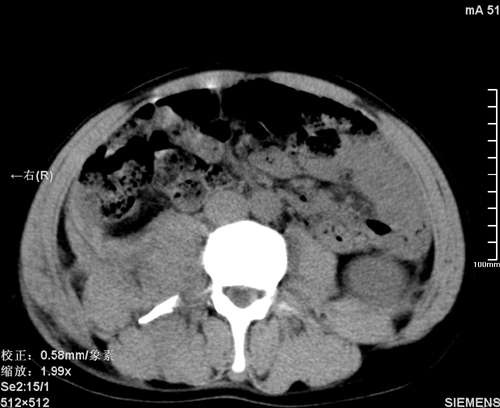

以下是引用qiushi在2008-3-28 12:00:00的发言:[br]腹膜后血肿,所见腰椎横突骨折.[br]建议上传骨窗、腰椎扫描.

以下是引用tao772在2008-3-28 12:29:00的发言:[br]右侧腹膜后积血,右侧腰大肌挫伤,右侧部分横突骨折. 肾脏最好报一下挫伤,必要时增强。